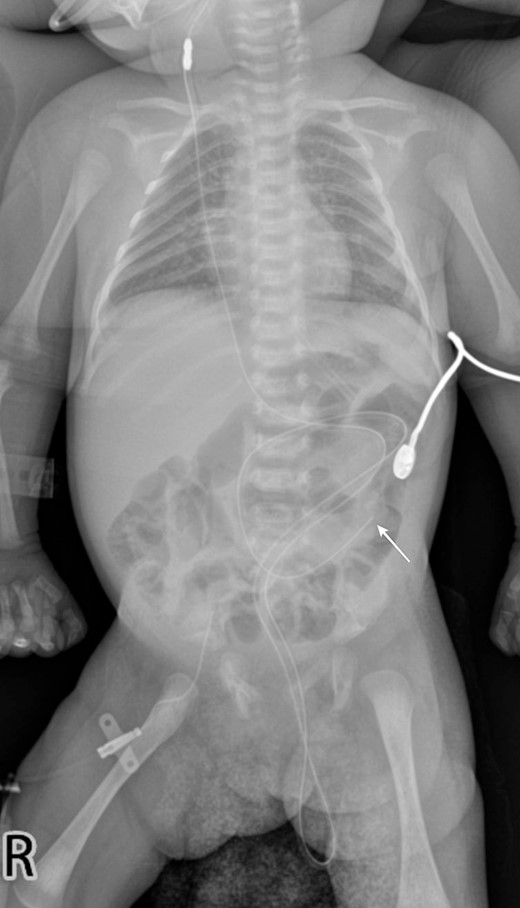

A 1-month-old female infant presented with a protruding tube from the anal orifice, 1 month following VP shunt placement for congenital hydrocephalus. She displayed no signs of shunt malfunction or gastrointestinal disturbances. Examination confirmed the presence of the distal VP shunt tube protruding from the anus (Fig. 1), as verified by babygram X-ray (Fig. 2). Immediate laparotomy was undertaken to remove the shunt. Intraoperatively, it was revealed that the shunt had breached a perforation in the descending colon. The proximal shunt was disconnected and removed, while the distal segment was retracted into the abdomen and gently guided through the anus, followed by meticulous abdominal closure. The decision was made not to close the colonic perforation, as the surrounding fibrous tissue was deemed sufficient to contain abdominal contents. Postoperatively, the patient underwent a 1-day fasting period before a gradual dietary reintroduction. Discharge ensued after 7 days, with prophylactic antibiotics administered. Subsequent follow-up appointments demonstrated no complications, with the patient maintaining shunt independence and exhibiting good health.

A babygram X-ray demonstrates the distal tip of the shunt positioned at the level of the left paravertebral L4 (white arrow), with a portion of the shunt extending downward and protruding from the abdominal cavity.